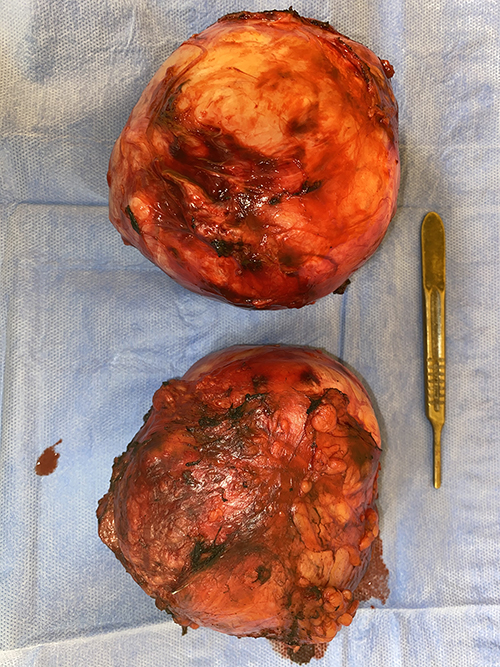

أعلن الدكتور طارق الجمال رئيس جامعة أسيوط عن نجاح فريق طبي بمعهد جنوب مصر للأورام في إنقاذ حياة مريض في الثلاثينات من عمره وذلك بإجراء جراحة ناجحة تم من خلالها استئصال ورم خبيث بالبطن خلف الكليه اليسرى وآخر بالصدر خلف الرئة اليسرى والقلب والذي يأتي في إطار استمرار الخدمات الصحية والطبية الهائلة المقدمة داخل المعهد لأكثر من 40 ألف مريض سنويا من مختلف الأعمار ومن مختلف محافظات الصعيد . وأوضح الدكتور سامي عبد الرحمن عميد معهد جنوب مصر للأورام أن المريض تم استقباله وكان يشتكى من آلام بالبطن وبالكشف علية وفحصه و مناظرة الأشعة تحت إشراف الدكتور حسين فخري البحيرى أستاذ جراحة الأورام بالمعهد و تبين وجود ورم بالبطن خلف الكليه اليسرى حجمه حوالي 12X 15 سم مسبباَ ضغط على الحجاب الحاجز وشريان الأورطى وورم آخر بالصدر خلف الرئة اليسرى والقلب يبلغ حجمه حوالي 10 X15 سم . وأشار الدكتور حسين فخري البحيرى أن الفريق الطبي المعاون له ضم كلاَ من طبيب عماد سعد وطبيب محب إدوارد المدرسين المساعدين بقسم جراحة الأورام وبالتعاون مع فريق طبي من جراحة الصدر والقلب بقيادة الدكتور حسين الخياط أستاذ مساعد جراحة الصدر والقلب وطبيب محمود محمد مدرس مساعد جراحة القلب والصدر وتم تخدير المريض تحت أشراف الدكتور خالد فارس الأستاذ المساعد بقسم تخدير الأورام بالمعهد وطبيب أحمد عبد الحميد وطبيبه سلمى الزناتى وطبيبة ميرنا إسماعيل المدرسين المساعدين بقسم تخدير الأورام وتم استئصال ورم البطن مع الحفاظ على الكليه اليسرى و الطحال البنكرياس والشريان الأورطى وأيضا استئصال ورم الصدر مع الحفاظ على الرئة اليسرى والقلب وإعادة إصلاح الحجاب الحاجز مؤكداً أن المريض في حالة صحية جيدة ولا يزال يتلقى الرعاية الصحية اللازمة له عقب الجراحة بالمعهد.

فريق طبي بجامعة أسيوط ينجح في إنقاذ حياة مريض باستئصال ورم خبيث خلف الكليه اليسرى و آخر خلف الرئة اليسرى و القلب